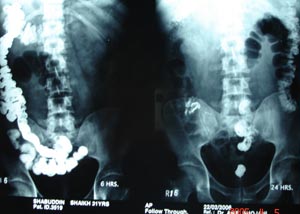

Barium sulphate as the contrast medium for gastrointestinal tract: It is an inert medium & produces excellent opacification. GI contrast.